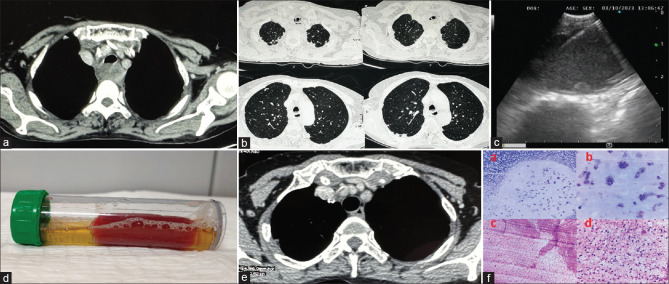

Abstract: Mediastinal cysts can occasionally cause severe respiratory symptoms. A 60-year-old female smoker presented with acute hypercapnic respiratory failure. Imaging revealed a posterior mediastinal cyst compressing the trachea. Bronchoscopic ultrasound-guided fine needle aspiration (EUS-B FNA) provided both diagnostic clarity and symptomatic relief. This case underscores the importance of considering mediastinal cysts in differential diagnoses of acute respiratory distress and demonstrates the efficacy of EUS-B FNA for both diagnosis and immediate therapeutic intervention.